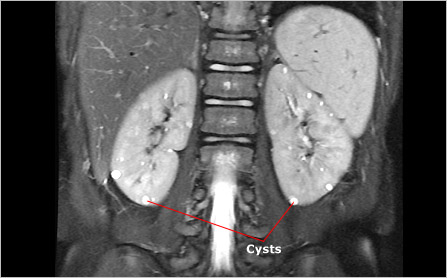

Renal cysts occur in approximately 20 percent of people with TSC. Doctors recognize two types of renal cysts. The more common of the two typically remains small (2 mm to 1 cm in diameter), appears as a single cyst or in small numbers, and has little effect on kidney function. The second type, which affects 2 to 3 percent of people with TSC, is large (1 cm to 5 cm in diameter), often occurs in large numbers, and typically affects both kidneys. This condition is similar to a disorder called polycystic kidney disease and results from a particular type of TSC mutation. In this case, a large portion of DNA on chromosome 16 is altered or deleted, affecting both the TSC2 gene and an adjacent gene called the polycystic kidney disease (PKD1) gene. People who have this condition tend to develop many cysts that grow and ultimately crowd renal tissue and compromise kidney function. Because renal cysts can occur in people with polycystic kidney disease who do not have TSC, they are considered a minor feature in the diagnostic criteria for TSC.